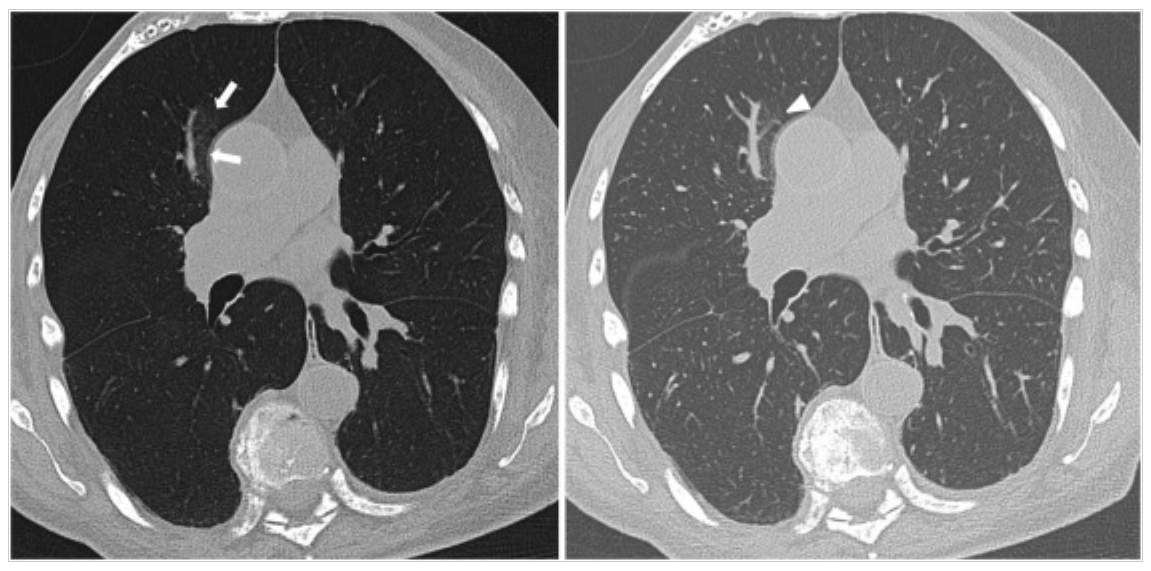

Minimum Intensity Projection (MinIP)

Her açıdan en düşük dansite değerine sahip voksellerin birleştirilerek iki boyutlu görüntüye aktarılması ile oluşturulur. Sarus PACS MinIP aracı ile sadece hava dansitesine eşit ya da […]